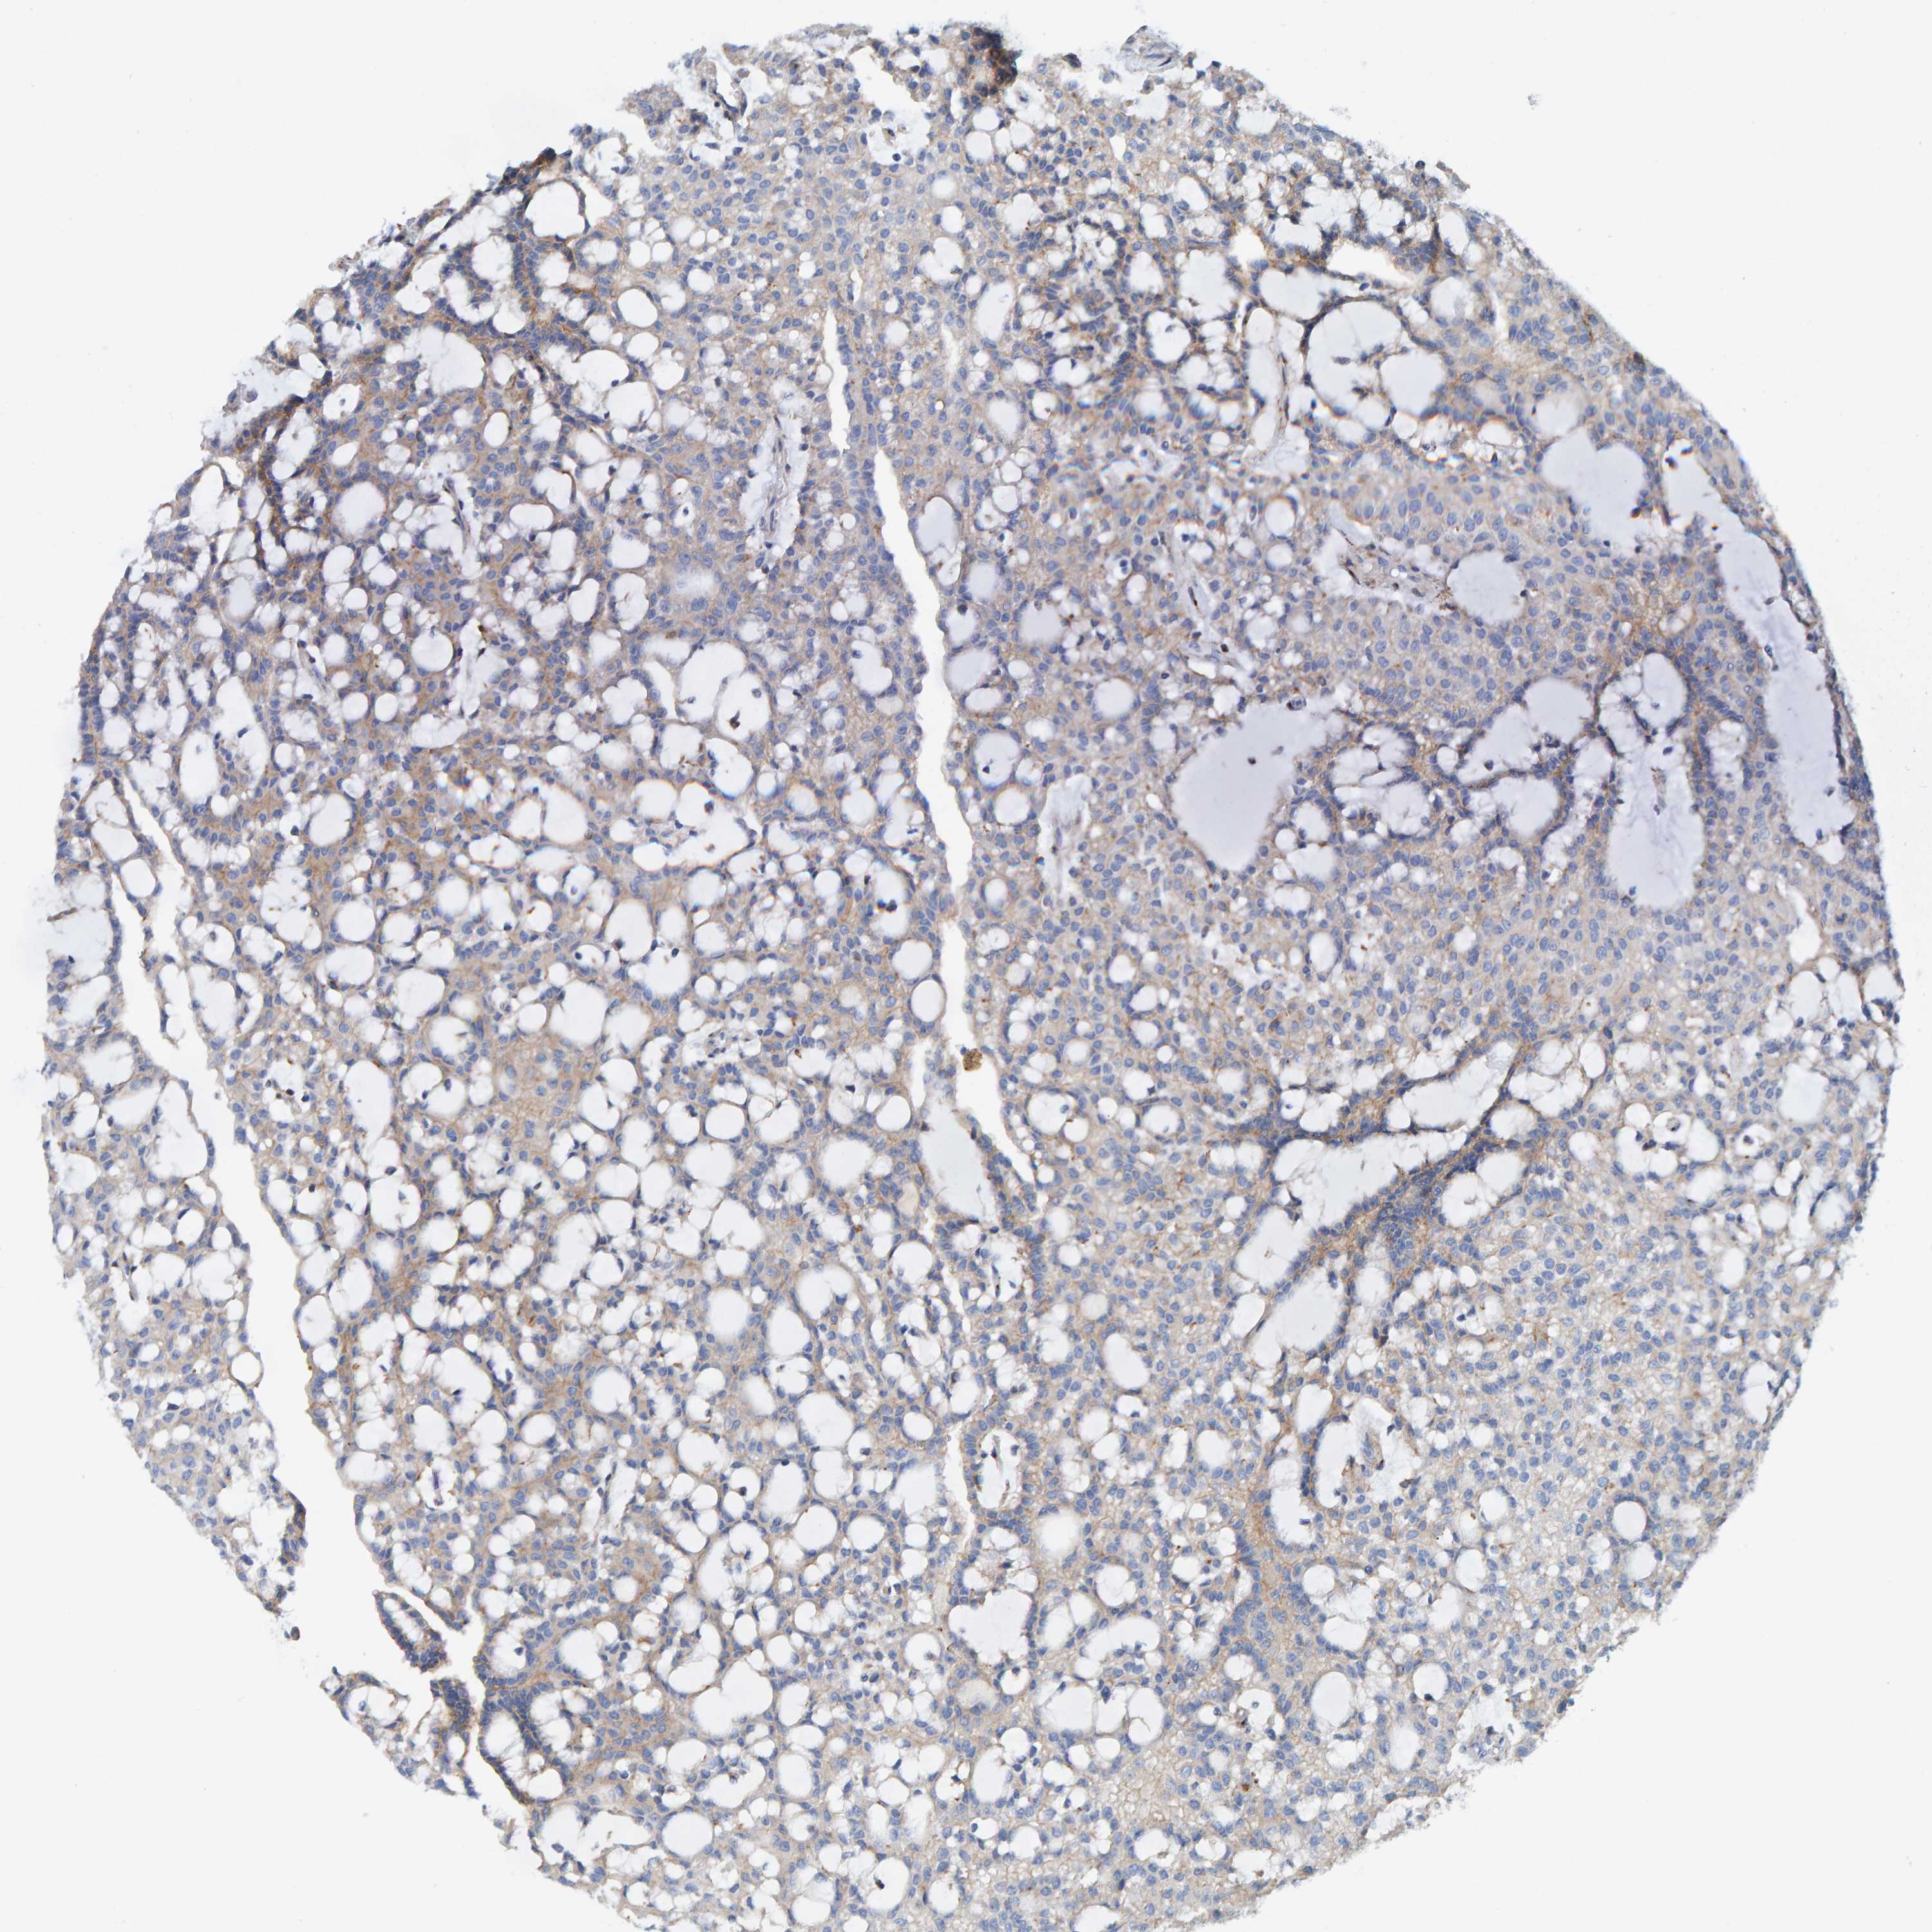

KIDNEY RENAL CLEAR CELL CARCINOMA (TCGA) - Interactive survival scatter ploti

The Survival Scatter plot shows the clinical status (i.e. dead or alive) for all individuals in the patient cohort, based on the same data that underlies the corresponding Kaplan-Meier plots. Patients that are alive at last time for follow-up are shown in blue and patients who have died during the study are shown in red.

The x-axis shows the expression levels (FPKM) of the investigated gene in the tumor tissue at the time of diagnosis. The y-axis shows the follow-up time after diagnosis (years). Both axes are complimented with kernel density curves demonstrating the data density over the axes. The top density plot shows the expression levels (FPKM) distribution among dead (red) and alive patients (blue). The right density plot shows the data density of the survived years of dead patients with high and low expression levels respectively, stratified using the cutoff indicated by the vertical dashed line through the Survival Scatter plot. This cutoff is automatically defined based on the FPKM cutoff that minimizes the p-score. The cutoff can be changed by dragging the vertical line or by entering a cutoff value in the square labeled "Current cut-off".

Under the Survival Scatter plot the p-score landscape (black curve; left axis) is shown together with dead median separation (red curve; right axis). Dead median separation is the difference in median mRNA expression between patients who have died with high and low expression, respectively. It is calculated as follows: median FPKM expression of dead patients with high expression - median FPKM expression of dead patients with low expression. This is intended to aid the user in visually exploring custom cutoffs and the associated p-scores and dead median separation.

Individual patient data is displayed and can be filtered by clicking on one or more of the category buttons on the top of the page. Categories describing expression level and patient information include: high, low, alive, dead, female, male and tumor stages. The scale of the x-axis can be toggled between linear and log-scale by clicking on the "x log" button. Mouse-over function shows TCGA ID, patient information and mRNA expression (FPKM) for each patient.

& Survival analysisi

Kaplan-Meier plots summarize results from analysis of correlation between mRNA expression level and patient survival. Patients were divided based on level of expression into one of the two groups "low" (under cut off) or "high" (over cut off). X-axis shows time for survival (years) and y-axis shows the probability of survival, where 1.0 corresponds to 100 percent.

LRP1 is potential prognostic, high expression is favorable in Kidney Renal Clear Cell Carcinoma (TCGA)

Best expression cut offi

Based on the FPKM value of each gene, patients were classified into two groups and association between prognosis (survival) and gene expression (FPKM) was examined. The best expression cut-off refers the FPKM value that yields maximal difference with regard to survival between the two groups at the lowest log-rank P-value. Best expression cut-off was selected based on survival analysis .

When clicking on this number, the vertical dashed line indicating cut-off, the interactive survival plot, and the Kaplan-Meier curve will be adjusted to show results based on the best expression cut-off.

: 14.9

Median expressioni

Median expression refers to the median FPKM value calculated based on the gene expression (FPKM) data from all patients in this dataset. When clicking on this number, the vertical dashed line indicating cut-off, the interactive survival plot, and the Kaplan-Meier curve will be adjusted to show results based on the median expression.

: N/A

Median follow up timei

Median follow up time refers to the median time (years) after diagnosis with this type of cancer, based on clinical data from all patients in this dataset.

P scorei

Log-rank P value for Kaplan-Meier plot showing results from analysis of correlation between mRNA expression level and patient survival.

N/A

5-year survival highi

5-year survival for patients with higher expression than the expression cutoff.

For melanoma and glioma, 3-year survival is shown.

5-year survival lowi

5-year survival for patients with lower expression than the expression cutoff.

TCGA RNA samplesi

RNA-seq data is reported as average FPKM (number Fragments Per Kilobase of exon per Million reads), generated by the The Cancer Genome Atlas (TCGA) .

Normal distribution across the dataset is visualized with box plots, shown as median and 25th and 75th percentiles. Points are displayed as outliers if they are above or below 1.5 times the interquartile range. FPKM values of the individual samples are presented next to the box plot.

Average pTPM 30.7

Number of samples 521